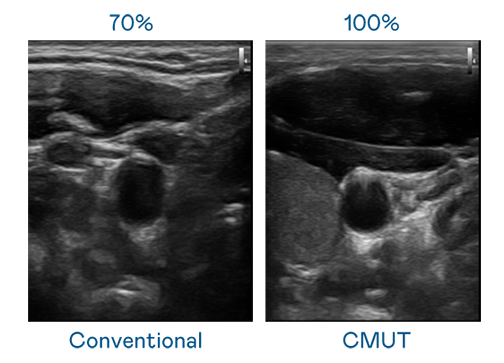

CMUT 技术是一种用电容式微机电元件来产生超音波讯号的技术。与传统 PZT 压电式技术相比,CMUT 频宽增加 30%,更宽频的超音波讯号让影像解析度大幅提升,是实现高影像品质医疗超音波扫描、促进精准医疗发展的关键技术。

大频宽带来超清晰影像

超音波影像的解析度高低,首先取决于探头能发出的讯号频宽。JJB电竞 CMUT 可提供高清晰的超音波讯号,提供高频宽、高灵敏度、影像纹理细节更高的超音波影像,协助医护人员缩短影像判读时间及利用精准的医疗影像进行诊断。